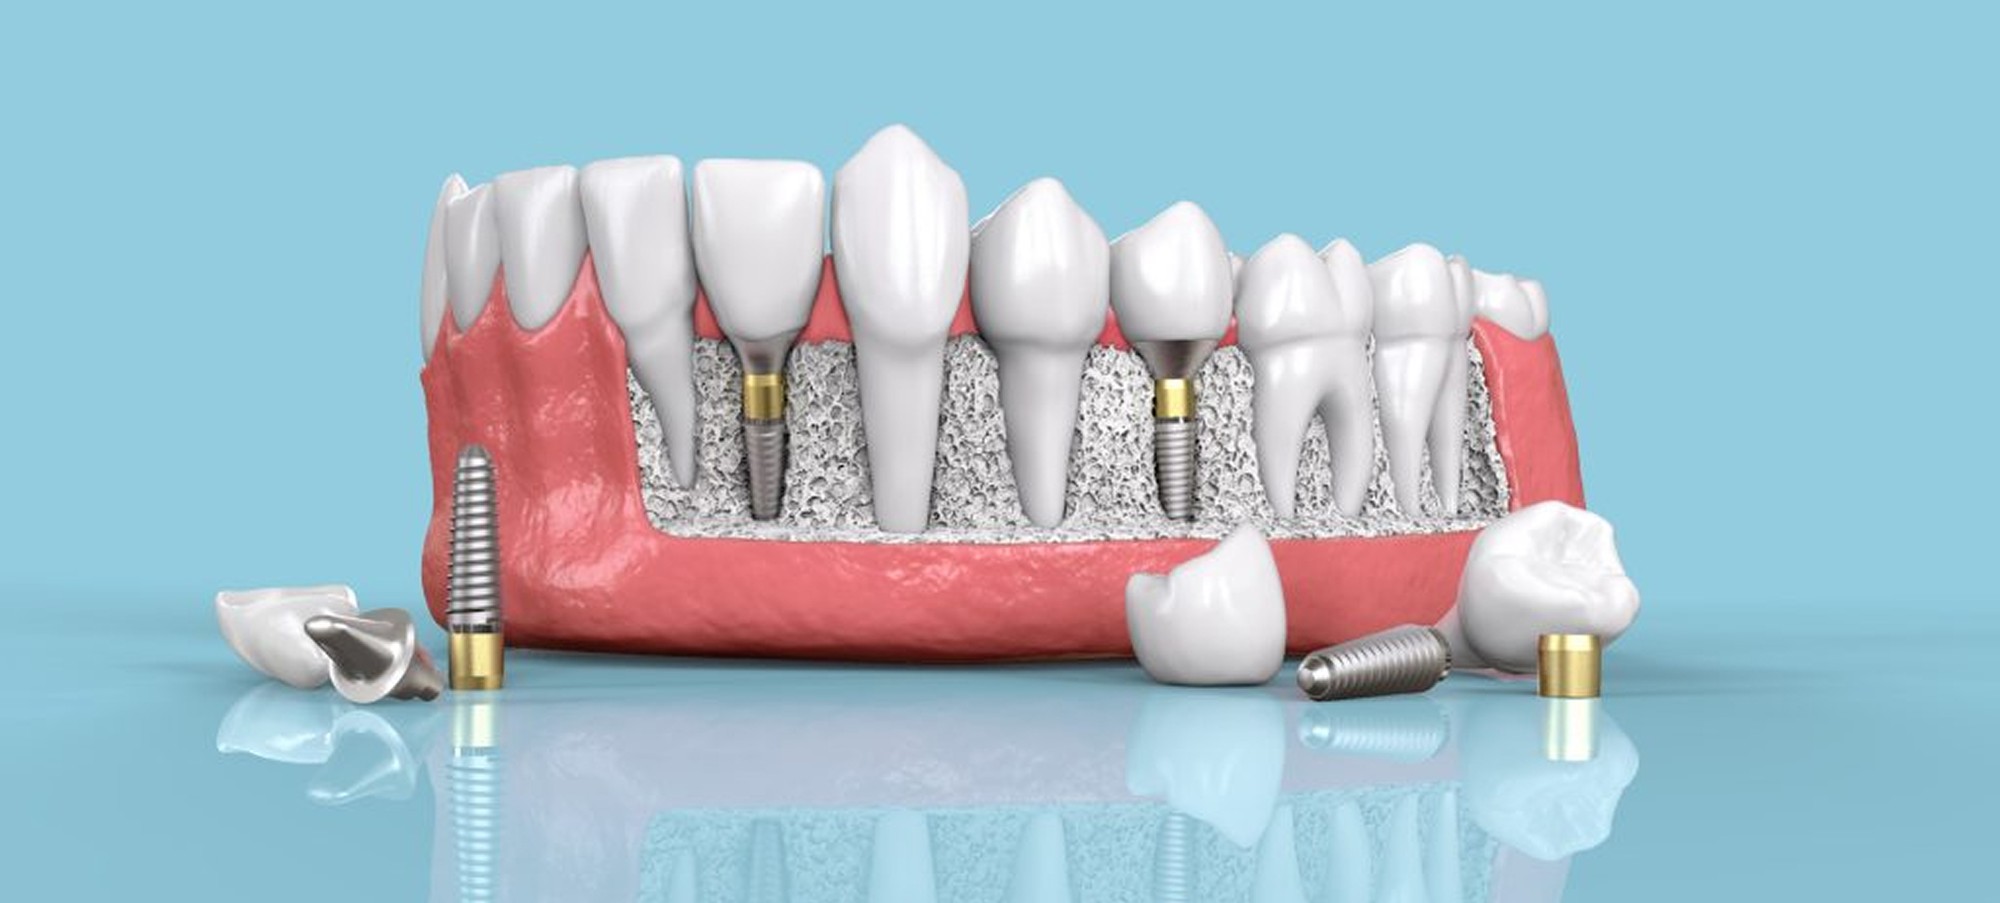

Parker Family Dental is offering implant placement and restoration. By incorporating 3D radiograph technology with CAD CAM technology we have the capability to first perform the implant surgery digitally before performing the surgery live. Once the implant placement is in perfect position digitally a surgical guide can be milled with our CAD CAM machine for exact placement of the implant. This allows for greater predictability and safety for the patient. This technology also allows for the implant to be in perfect position for the dental crown to function with full capability. Before the implant is placed the crown is already digitally created and the implant is aligned for perfect fit and performance. The aligning of these new technologies makes Parker Family Dental your one stop shop for all your implant needs.

Following surgery and the adequate healing time the proper implant crown and abutment are attached to the implant for the final prosthesis.